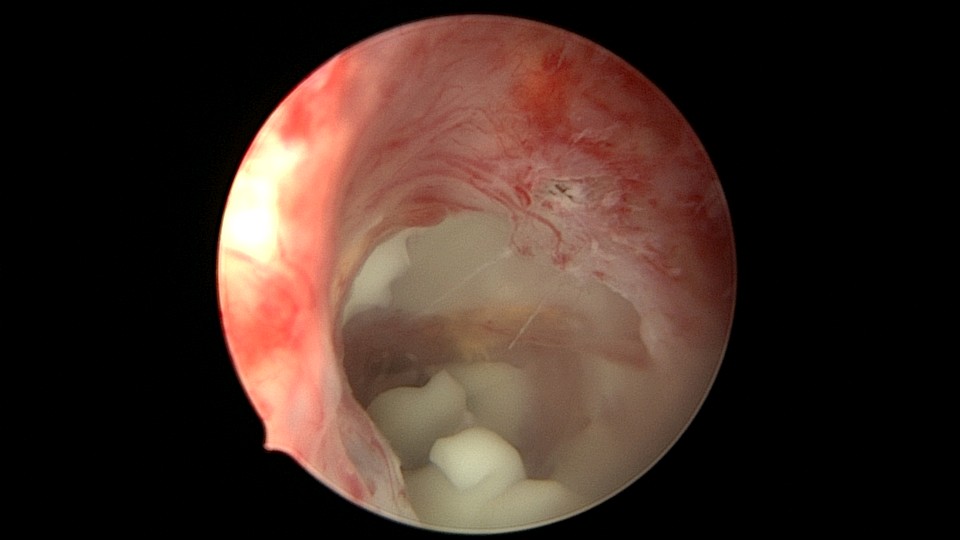

患者56岁,G3P1,顺产1次。安环20+年,绝经10年,下腹坠胀不适1周,B超提示子宫后位,宫内无回声区2.4cm×1.5cm。宫颈外口见节育环尾丝,环纵臂卡在宫颈管内,宫腔镜难以进入宫腔,取环后看到宫腔粘稠白色脓液,宫腔左侧前后壁粘连,膨宫液冲洗脓液,宫腔无其他异常。